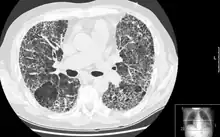

Diagnóstico

A espirometria permite identificar que se trata de uma doença pulmonar restritiva, mas a radiografia(como raio X) do tórax pode não ser suficiente para encontrar cicatrizes nos pulmões, sendo assim recomendado uma tomografia computadorizada de alta resolução para confirmar a presença da fibrose.[3]